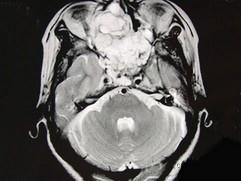

女性,41岁,鼻腔流脓涕3年,鼻部面部肿胀1年,近来加重,MRI检查如图,请选择最可能诊断 ( )